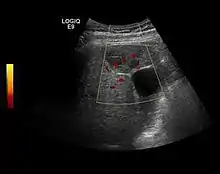

HCC appearance on 2D ultrasound is that of a solid tumor, with imprecise delineation, with heterogeneous structure, uni- or multilocular (encephaloid form). An "infiltrative" type is also described which is difficult to discriminate from liver nodular reconstruction in cirrhosis. Typically HCC invades liver vessels, primarily the portal veins but also the hepatic veins . Doppler examination detects a high speed arterial flow and low impedance index (correlated with described changes in tumor angiogenesis). The spatial distribution of the vessels is irregular, disordered. CEUS examination shows hyperenhancement of the lesion during the arterial phase. During the portal venous phase there is a specific "wash out" of ultrasound contrast agent (UCA) and the tumor appears hypoechoic during the late phase. Poorly differentiated tumors may have a stronger wash out leading to an isoechoic appearance to the liver parenchyma during portal venous phase. This appearance was found in approx. 30% of cases. The described changes have diagnostic value in liver nodules larger than 2 cm.

Spectral Doppler characteristics of early HCC overlap those of the dysplastic nodule, as they are represented by the presence of portal venous signal type or arterial type with normal RI (well differentiated HCC) or increased RI (moderately or poorly differentiated HCC). The CFM exploration identifies a chaotic vessels pattern.